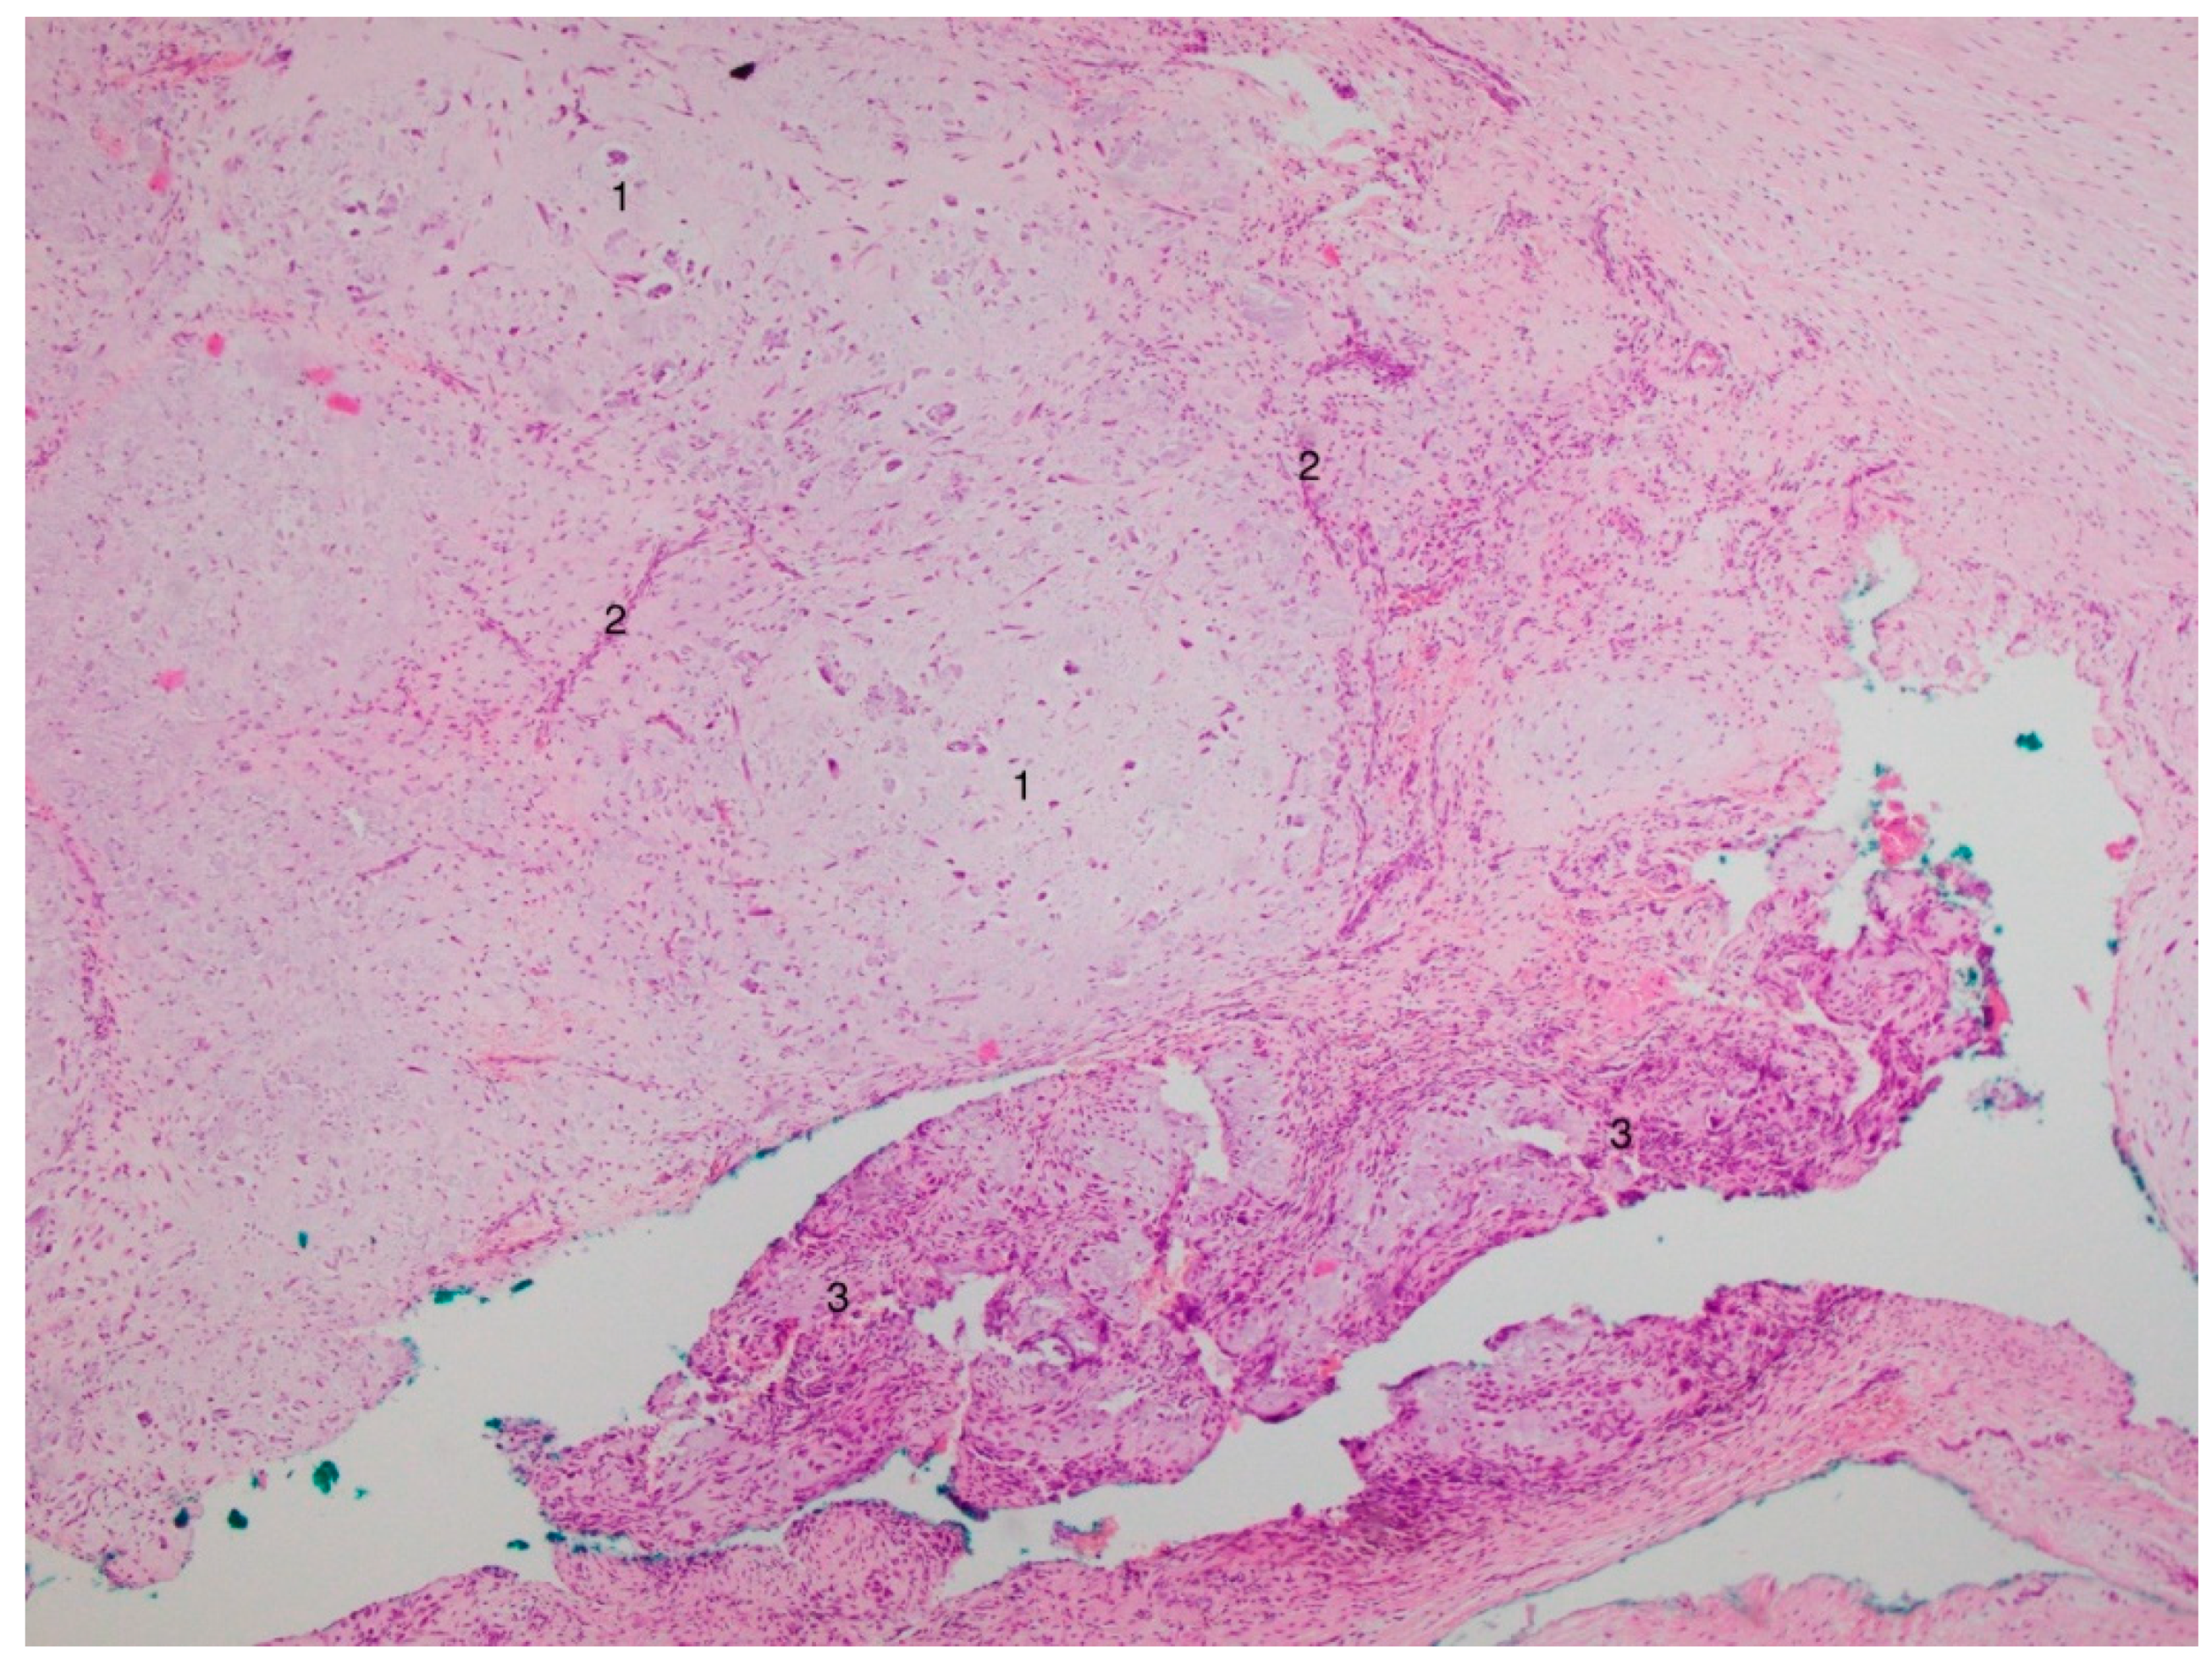

3. Results